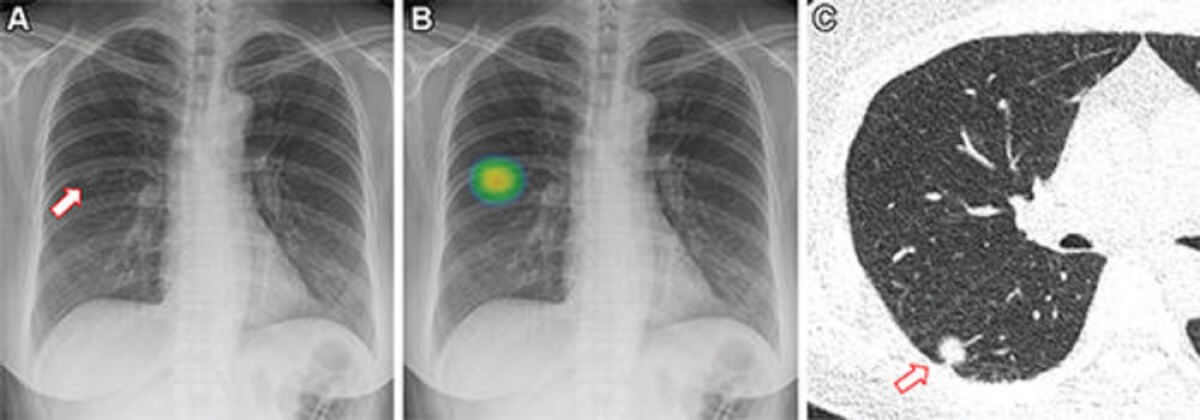

Images in a 73-year-old man who underwent chest radiography and low-dose CT for health checkup purposes and was allocated to the non–artificial intelligence (AI) group. (A) Frontal chest radiograph shows a small nodular opacity (arrow) in the left upper lung zone, which was missed by the designated reporting radiologist. (B) Axial, noncontrast, low-dose chest CT scan shows a 9-mm solid nodule (arrow) in the left upper lobe. The nodule showed low metabolism at PET and decreased in size at follow-up CT. It was confirmed to be an inflammatory nodule. (CREDIT: Radiological Society of North America)